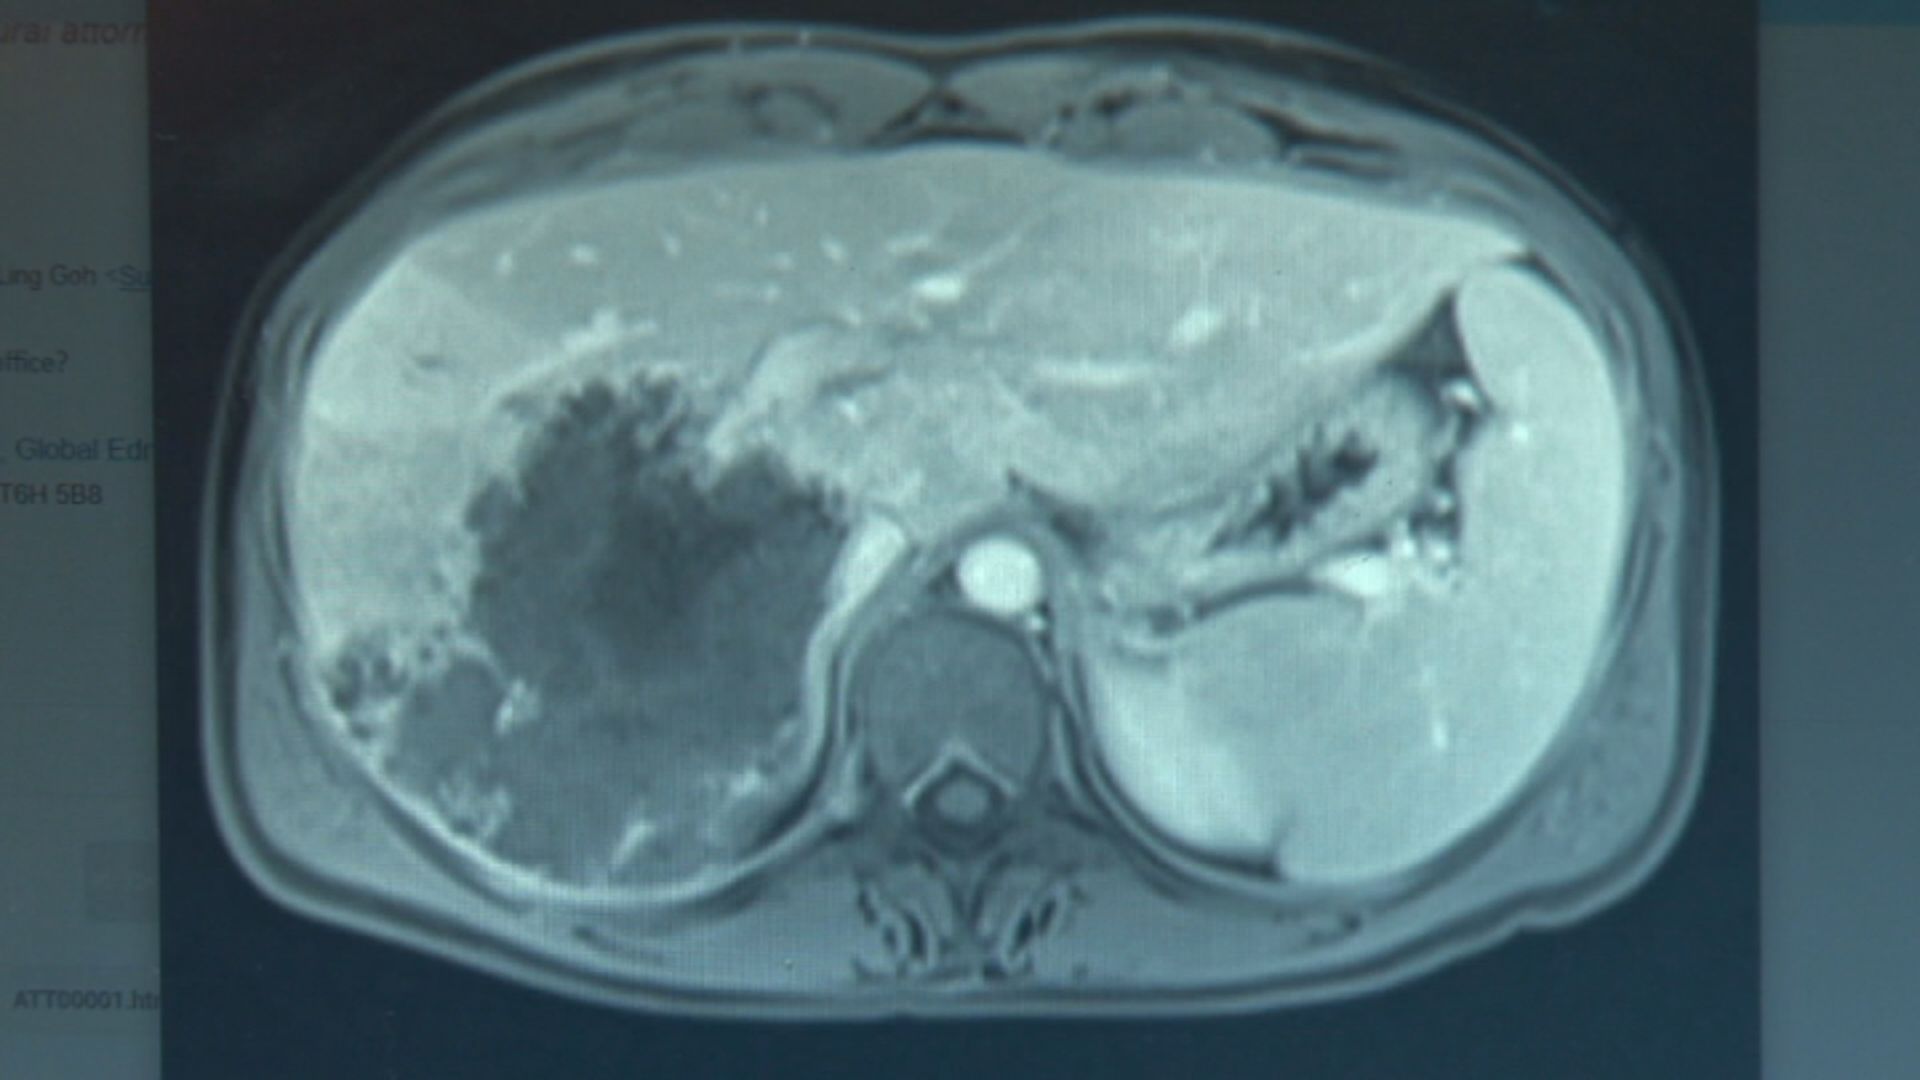

Magnetic resonance image of large, dark mass in Armstrong’s liver. Cassidy Armstrong

In November of 2019, the 36-year-old started having severe pain near her ribs and noticed she was losing weight. An MRI revealed a mass the size of a grapefruit in her liver. She was diagnosed with a rare, terminal liver cancer.

Surgeons removed 65 per cent of her liver, her entire gallbladder and some nodules from her lungs. Then a biopsy revealed the mass was actually a large cyst created by the tapeworm Echinococcus multilocularis.